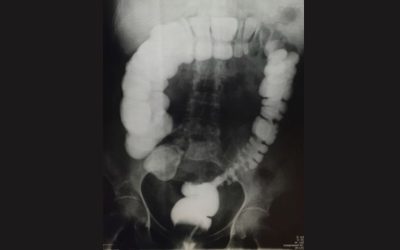

Lavement baryté

Il s’agit d’un examen radiographique (rayons X) permettant d’explorer le colon (gros intestin) et le rectum.